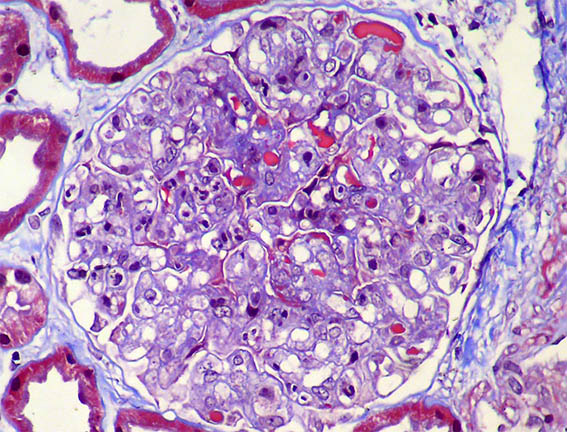

A 62-year-old woman is evaluated for erythema on both legs that has been developing for several weeks. There is no personal pathological history. On physical examination, they found systemic arterial hypertension, edema of the lower limbs, purpuric lesions on both legs, and Raynaud's phenomenon. In paraclinical tests, the hemoleukogram is normal; serum creatinine: 2.1 mg/dL, BUN: 39 mg/dL. ANA, anti-DNA, and ANCA: negative. C3: 82 mg/dL (84-180) and C4: 4.1 mg/dL (12-40). HIV and hepatotropic viruses: negative. In urinalysis there is microhematuria, leukocytes: 5/hpf, proteinuria: 4.2 g/24 hours, with mild hypoalbuminemia.

Figure 4. PAS, X400.

Figure 5. Masson's trichrome stain, X400.

Figure 6. Masson's trichrome stain, X400.

Figure 7. Methenamine-silver stain, X400.

Figure 8. Direct immunofluorescence for IgG, X400.

Figure 9. Direct immunofluorescence for kappa light chain, X400.

Figure 10. Direct immunofluorescence for lambda light chain, X400.

In immunofluorescence there is also positivity for C3 and, somewhat weaker, for C1q. IgA and IgM: Negative.